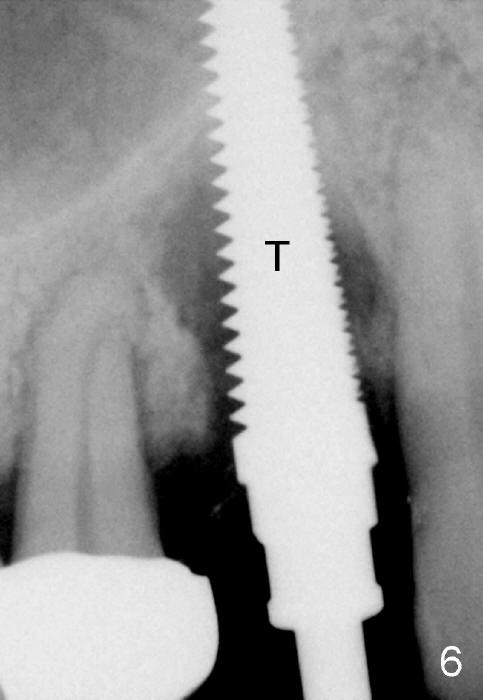

In spite of large periapical radiolucency (Fig.1 *), osteotomy is easier than expected. Use 2 mm pilot drill, 2.5-3.5 mm reamers from 14 mm (bottom of the socket) to 17 mm (sinus floor). The initial point for osteotomy at the bottom of the socket is easy to establish, because it is flat. By the time 5x20 mm tap is inserted, it is palatal (Fig.5). It is mandatory because the buccal plate has been perforated. The tap has to be inserted deeper (from 17 mm to 20 mm, Fig.6) to achieve stability. Insertion torque of 5x20 mm implant (Fig.7 I) is > 60 Ncm. The implant remains palatal so that there is space for bone graft (Fig.8 *). But the bone graft is a little over packed; there is no room to place collagen dressing. The latter will be dislodged and bone graft will be lost if perio dressing is loose prematurely. The perio dressing may have to be re-applied. Depth of bone graft is deemed sufficient if the implant threads are covered. Maximum will be on the rough surface. Physiologically, bone does not extend to the gingival margin.